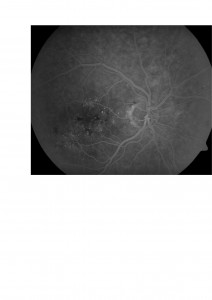

Destacamos asimismo que el tratamiento con láser está contraindicado cuando el edema macular asocia isquemia macular (es decir una mácula con falta de riego sanguíneo) ya que puede provocar una pérdida severa de la visión . Por este motivo destacamos que la angiografía fluoresceínica sigue siendo necesaria muchas veces antes de tratar un edema macular diabético. Esta prueba nos permite comprobar la perfusión de la mácula. Os mostramos un caso de un paciente tratado en otro centro en el que el tratamiento con láser provocó una pérdida severa con agudeza visual menor de 0,05.